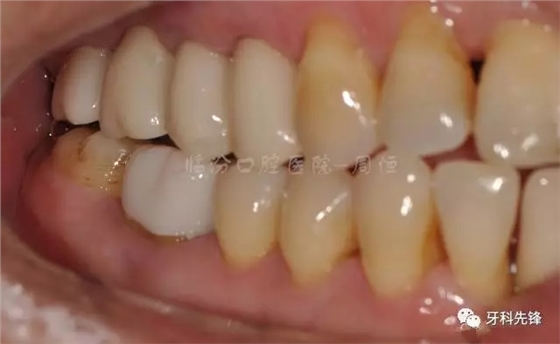

圖20牙體精修咬頜照

640.webp (24).jpg